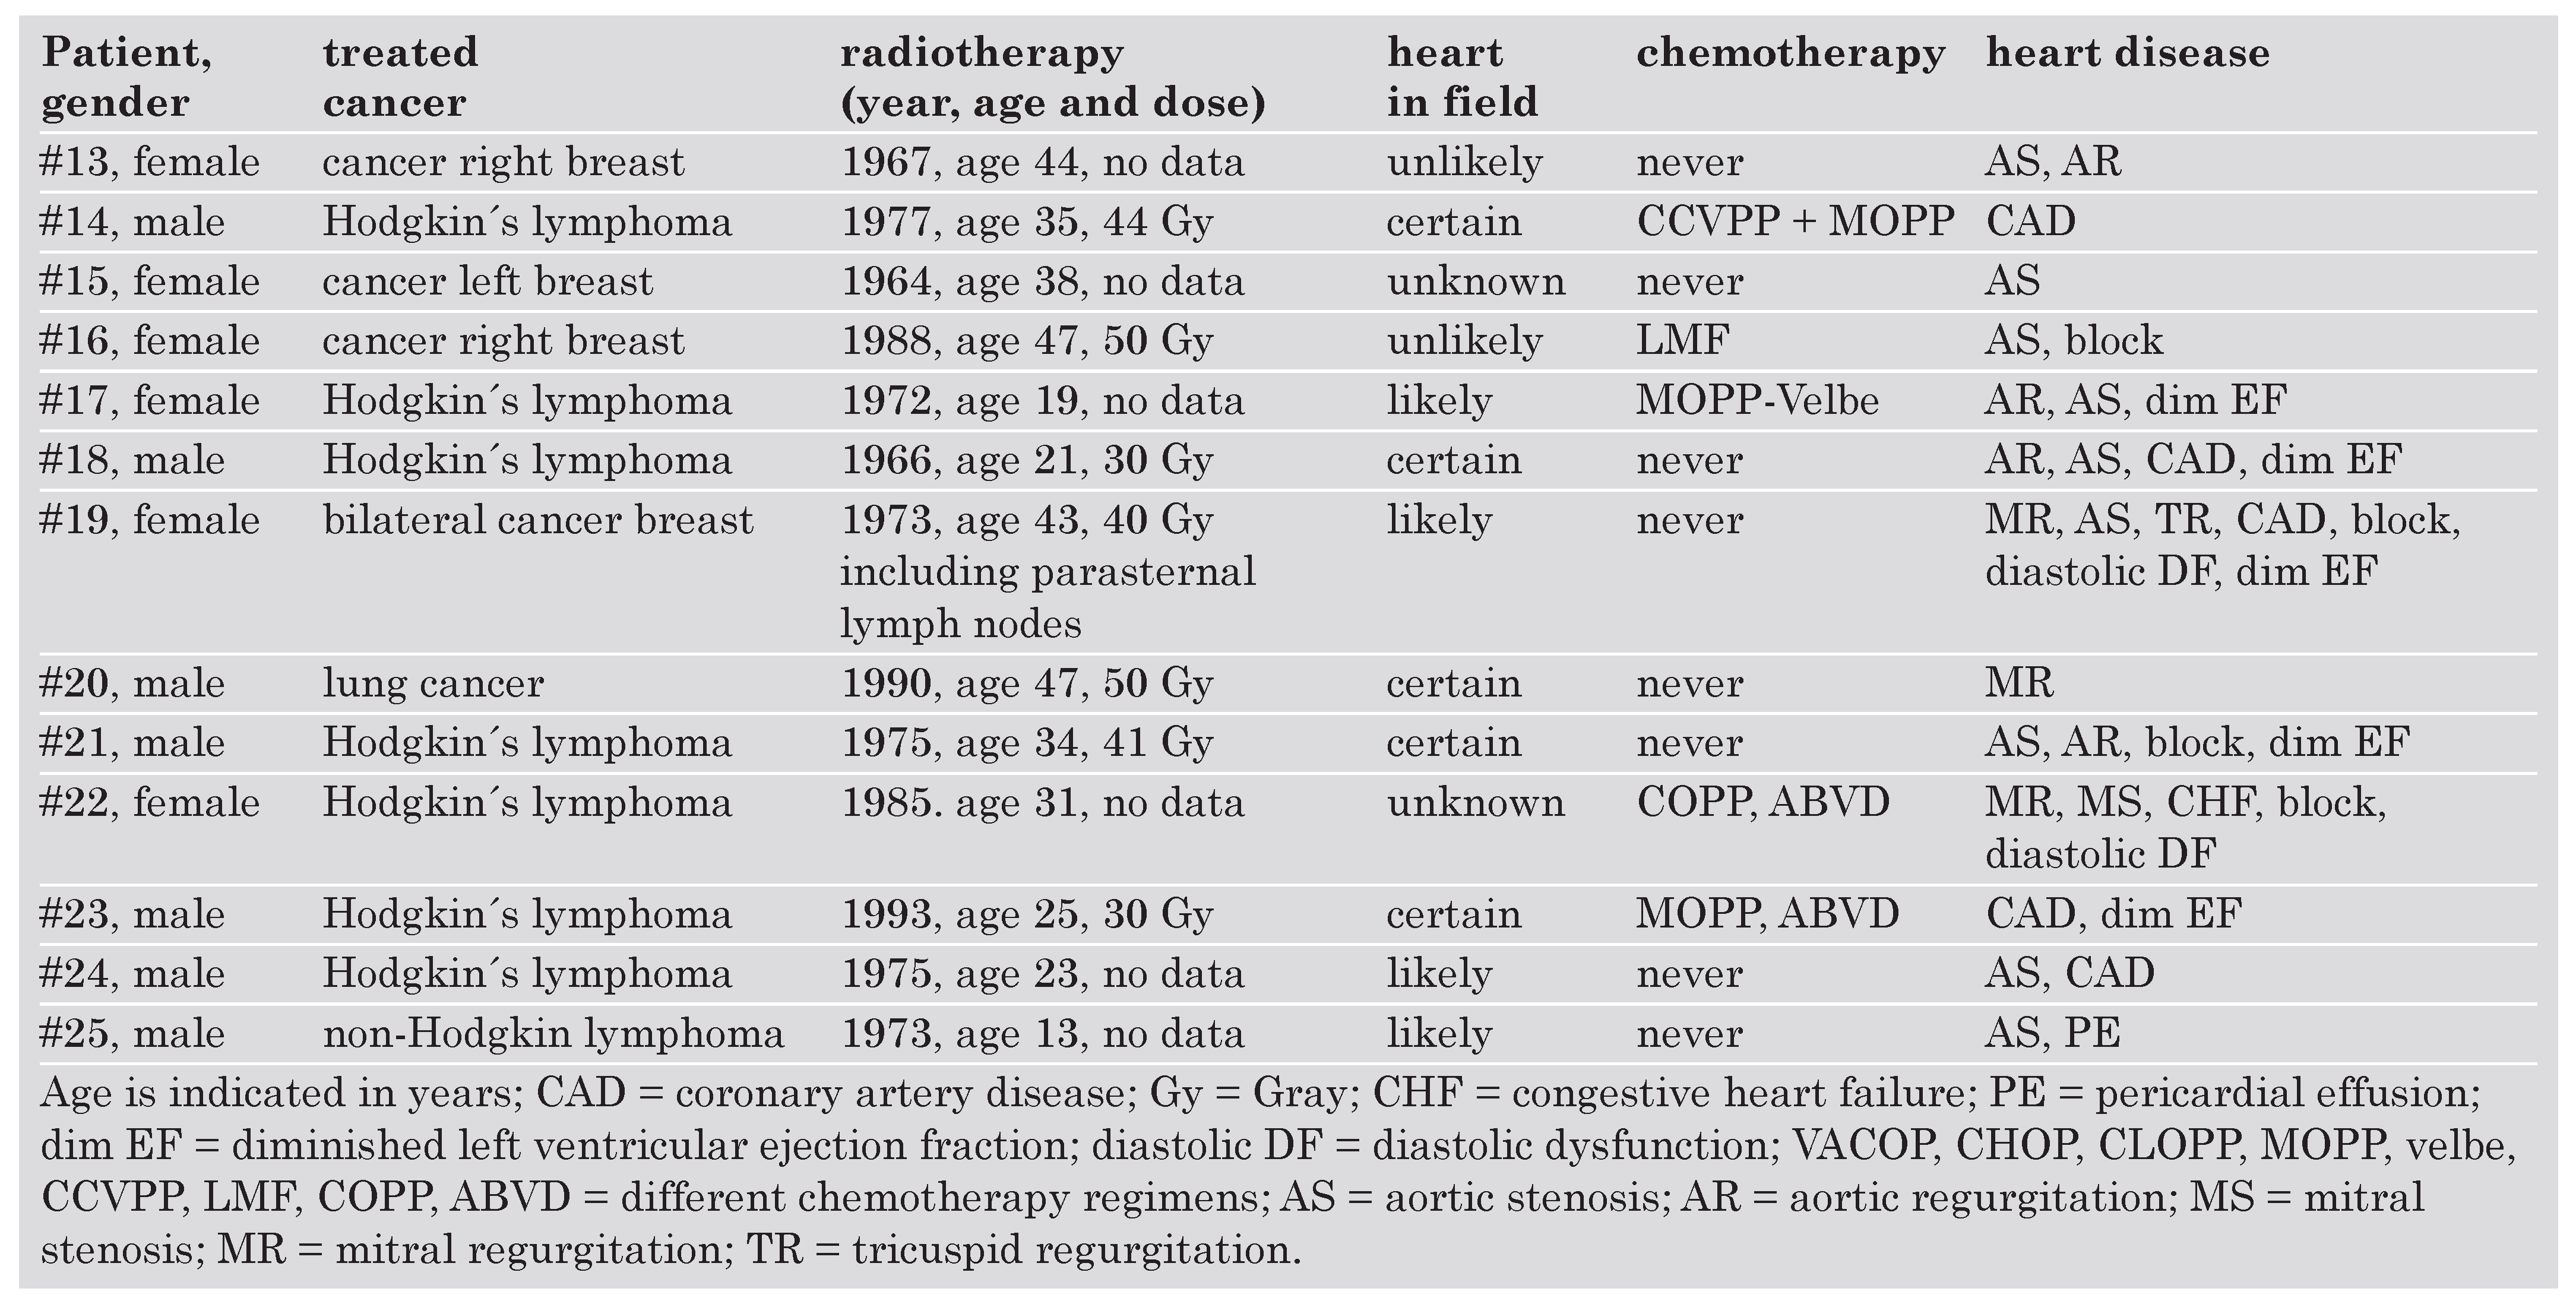

Clinical characteristics

|